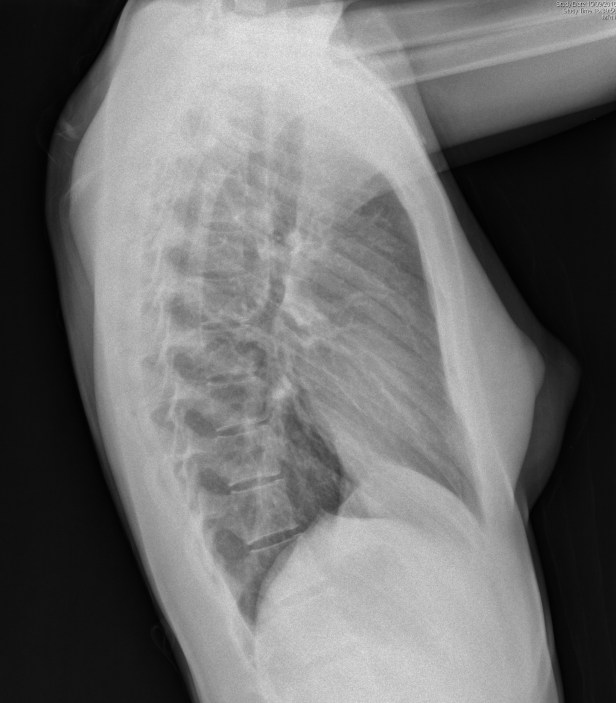

Cuando acabo de realizar la proyección PA (postero anterior) y la veo girarse es cuando veo aparecer el colgante frente a mí. Entonces encontré la ocasión de cerciorar qué efecto y qué apariciencia podría tener en la imagen. Al digitalizar la Rx PA no soy capaz de ver, a simple vista, el efecto. Pero al digitalizar la imagen de Rx lateral (más abajo) es cuando la veo sobre la piel de la paciente, a la altura del manubrio esternal. Me acerco a la paciente (que seguro leerá este artículo porque le comenté que lo publicaría) y le pido permiso para hacerle la fotografía, que pueda localizar la posición de la madera. Sio sitúa justo sobre la carina, al lado del botón aórtico.

Usando las herramientas en el visor digital (lupa, ventanas, etc..) no logro identificar al artilugio pero sin embargo sí se ve en la Rx lateral. Definitivamente, entiendo que, por la nitidez del resto de los cuerpos vertebrales, ‘está ahí, por debajo del manubrio esternal’, pero sólo logro ver la pequeña distorsión que produce al cambiar mínimamente los laterales del cuerpo de la 4º vértebra dorsal.

rx-tx-lt